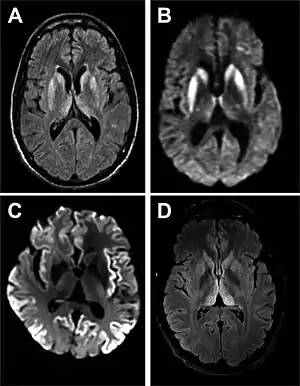

Imaging of the brain may be performed during medical evaluation, both to rule out other causes and to obtain supportive evidence for diagnosis. Imaging findings are variable in their appearance, and also variable in sensitivity and specificity.[41] While imaging plays a lesser role in diagnosis of CJD,[42] characteristic findings on brain MRI in some cases may precede onset of clinical manifestations.[43]

Brain MRI is the most useful imaging modality for changes related to CJD. Of the MRI sequences, diffuse-weighted imaging sequences are most sensitive. Characteristic findings are as follows:

- Focal or diffuse diffusion-restriction involving the cerebral cortex and/or basal ganglia. In about 24% of cases DWI shows only cortical hyperintensity; in 68%, cortical and subcortical abnormalities; and in 5%, only subcortical anomalies.[44] The most iconic and striking cortical abnormality has been called "cortical ribboning" or "cortical ribbon sign" due to hyperintensities resembling ribbons appearing in the cortex on MRI.[45] The involvement of the thalamus can be found in sCJD, is even stronger and constant in vCJD.[46]

- Varying degree of symmetric T2 hyperintense signal changes in the basal ganglia (i.e., caudate and putamen), and to a lesser extent globus pallidus and occipital cortex.[42]